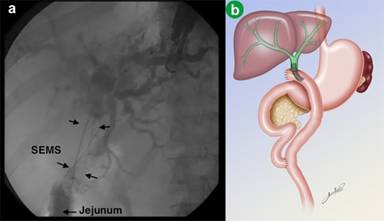

Contrast was injected to demonstrate the jejunal position of the guidewire, and showing the length of the stenosis (Figure 2). A 6 mm guidewire balloon dilation was performed, followed by the placement of a partially covered self-expandable metallic stent (10x60 mm, Wallflex, Boston Scientific, Natick, MA, USA), across the anastomosis (Figure 3). Adequate contrast drainage was observed (Figure 4).

|

Figure 4 a. Radiological image of the metal stent. b. Schematic picture demonstrating the final positioning of the self-expandable metal stent. |